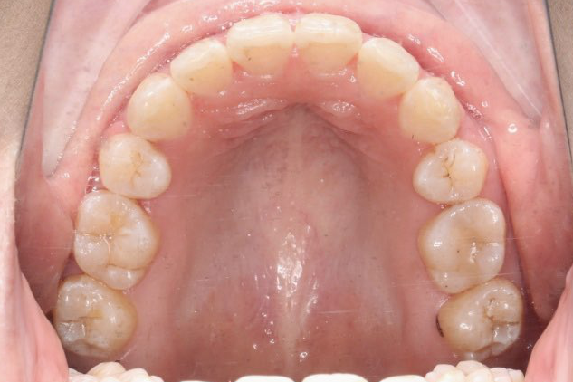

2018.11.14  术后磨牙尖牙I类关系,中线齐,覆合,覆盖正常

牙根基本平行,未见牙根吸收

2019.08.06  术后  10个月复查